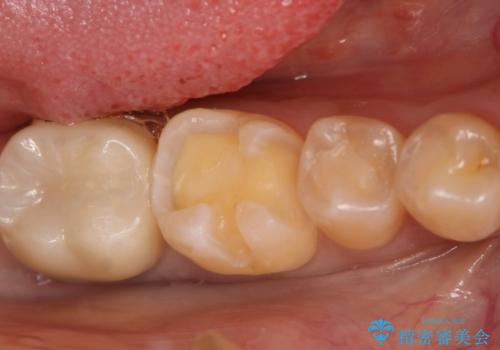

- 過去に他院で治療した部位が材料劣化を起こしていたため、セラミック治療を希望された患者様です。

切削量を考慮し、セラミックインレーを選択しました。

虫歯が深かったので、CRを詰めた上で形態を整えています。